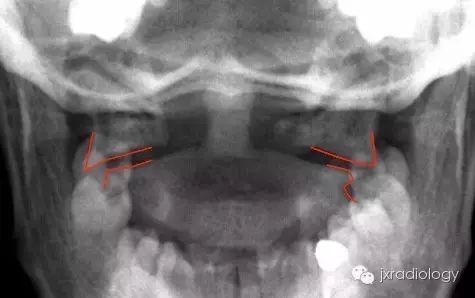

寰椎骨折又名Jefferson骨折(因由Jefferson于1920年首次报道,故此命名)。环形的寰椎遭受轴向压缩和头部向后、下转伸时,暴力经枕骨髁作用于寰椎侧块,并引起寰椎骨环爆裂(散)骨折。寰椎的前弓与后弓双侧骨折,以致侧块被挤压而向四周分离

主要介绍颈椎开口位的X线平片表现:开口位可发现寰椎左右增宽,且与齿突的距离双侧常呈不对称状。如双侧侧方移位总和超过7mm者,则表示寰椎横韧带断裂、寰椎骨折。

正位与齿状突对比似双侧开门样增宽,为此加深记忆,故得此名,如有不妥,敬请谅解(小编)。